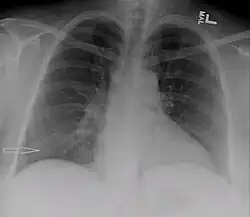

Right sided pleural effusion caused by urinothorax

Chest X-ray showing urinothorax disappearing after treatment

Treatment mainly consists of treating the underlying disorder of the genitourinary tract.[2] It requires a multidisciplinary team that includes a pulmonologist and urologist. A nephrostomy tube or Foley catheter can be used to relieve any underlying obstruction. Any injuries are repaired.[11] When the underlying disorder is addressed, the urinothorax rapidly resolves. Thoracic surgery is usually not needed,[4] especially if respiratory symptoms are minimal or nonexistent.[2] Pleurodesis is also ineffective.[11] A chest tube can be used to drain urine from the pleural cavity.[12]